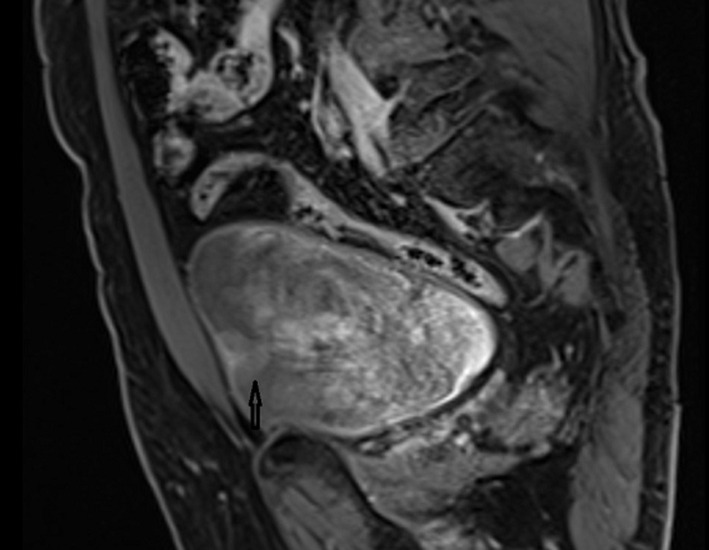

肾脏的功能受到其他器官疾病的影响。在这里,我们提出了一个肾功能正常的老年透析前患者,尽管有许多合并症,但肾脏学随访10年。患者男性,75岁,高血压病史15年,吸烟60包年,诊断为肌肉浸润性膀胱癌(MIBC)和左肾同步中央定位透明细胞肾细胞癌(ccRCC)。入院时患者估计肾小球滤过率(Glomerular Filtration Rate, eGFR) (CKD-EPI-cre)为54mL/min/1.73m2,左肾切除术后患者的eGFR降至35ml /min/1.73m2。经过10年的随访,患者的右肾功能正常,eGFR为24 mL/min/1.73m2,尽管进行了根治性膀胱切除术并尿路转移、根治性肾切除术、重度吸烟、心肾综合征、慢性阻塞性肺疾病和高血压。众所周知,高血压、吸烟、癌症、感染、肺病和心脏病等合并症会造成不可逆的肾脏损害,并会导致肾功能下降。这些合并症的适当和早期诊断和治疗可以使肾脏健康老化,而不需要透析。

Kidneys are functionally affected by the diseases of other organs. Here, we present an elderly predialysis patient with a functioning kidney for 10 years of nephrological follow-up despite many comorbidities. A 75-year-old male patient with a medical history of hypertension for 15 years and 60 pack years of cigarette smoking, was diagnosed as muscle invasive bladder cancer (MIBC) and synchronous centrally located clear cell renal cell carcinoma (ccRCC) in the left kidney. At admission, the patient had an Estimated Glomerular Filtration Rate (eGFR) (CKD-EPI-cre) of 54mL/min/1.73m2, after left nephrectomy eGFR of the patient decreased to 35 mL/min/1.73m2. After ten years of follow-up, the patient's right kidney had been functional with a eGFR of 24 mL/min/1.73m2 despite radical cystectomy with urinary diversion, radical nephrectomy, heavy smoking, [cardiorenal syndrome, chronic obstructive pulmonary disease, and hypertension. It is well known that comorbidities such as hypertension, smoking, cancers, infections, pulmonary and heart diseases contribute to irreversible kidney damage and are additive to decreasing kidney function. Appropriate and early diagnosis and treatment of these comorbidities permit healthy aging of the kidneys without the need for dialysis.